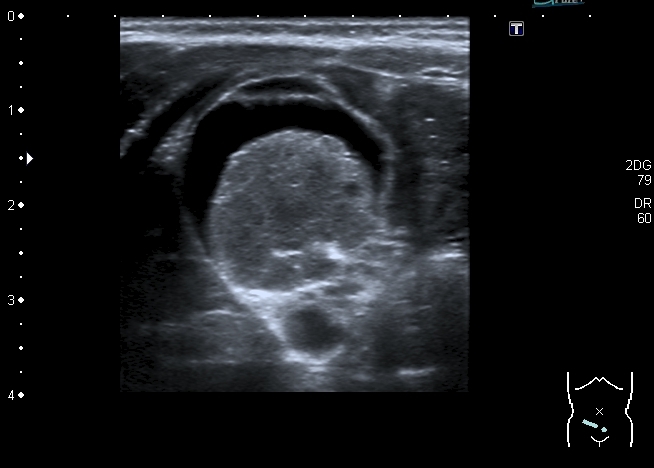

У девочки 5 месяцев ранее на УЗИ нашли образование в полости таза . С заключением киста яичника направлена к нам.

На УЗИ справа от мочевого пузыря - солидно - кистозное образование около 3 см. Образование прилежит к правому яичнику, который визуально не изменён, но смещается относительно его при движениях брюшной стенки Относительно яичника образование гиповаскулярное Выставил диагноз объёмного образования полости таза (дифференцировать энтерокистому и дермоид). Не думаю, что образование исходит из яичника, поэтому стартую тему в гастроэнтерологических исследованиях.

Затронул данную тему, т. к. считаю ультразвуковую семиотику образований яичников и придатков у детей мало изученной , но тем не менее достаточно важной. В моей личной практике клиницисты ставят основной вопрос: откуда образование. Если из яичника или придатков матки - лечат гинекологи. Если из кишечника - лечат хирурги. В данном случае маловероятна непосредственная связь образования с яичником из- за взаимной смещаемости, хотя кистозные тератомы м.б. на ножке. Из придатков матки в доступных мне источниках описаны два варианта образований 1) параовариальные кисты с тонкой стенкой без тканевого компонента - не похоже; 2) гидатида трубы - обычно поменьше.

Есть ещё вариант кисты брызжейки кишечника, рядом с образованием действительно петли тонкой кишки, но опять же не характерен тканевой компонент. Муцинозная\серозная цистаденома как правило более интимно связана с яичником.